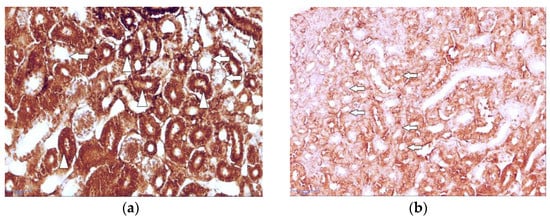

The results of the immunohistochemical study revealed the immunolocalization of the major glucose transporters in the kidney, SGLT1 and SGLT2, which were observed in the proximal renal tubules of the hen chickens in both study groups (Figure 3a and Figure 4a). In the group of healthy chickens, a strong expression of SGLT1 occurred in the apical part of the epithelial cells of the renal proximal tubules (Figure 3a).

Compared to the healthy birds, the expression of both of the studied antibodies was weaker in the T-2 toxin group, and the brush border membranes of the proximal tubule’s epithelial cells were irregular and damaged (Figure 3b and Figure 4b).

In the comparison of both of the studied antibodies, the staining of the renal tissue of the control group was more intense than that of the T-2 toxin group. The results of the repetitive IHC studies confirmed the results of the primary experiment. Furthermore, the expression of SGLT2 was observed to be much stronger than the staining of SGLT1. The results of the descriptive (eye visual) analysis of the expression of SGLT1 and SGLT2 in the proximal tubules, which was determined according to the intensity of the staining, are shown in Table 1.

Figure 3. Immunolocalization of the sodium-dependent glucose co-transporter-1 (SGLT1) in kidney tissue (a) in healthy 7-day-old chickens; note the strong expression of SGLT1 in the apical part of the epithelial cells of renal proximal tubules (arrowheads). Magnification 400×, scale bar 50 µm; (b) damaged brush border membranes of proximal tubule’s epithelial cells in intoxicated chicken (arrows). Magnification 400×, scale bar 50 µm.